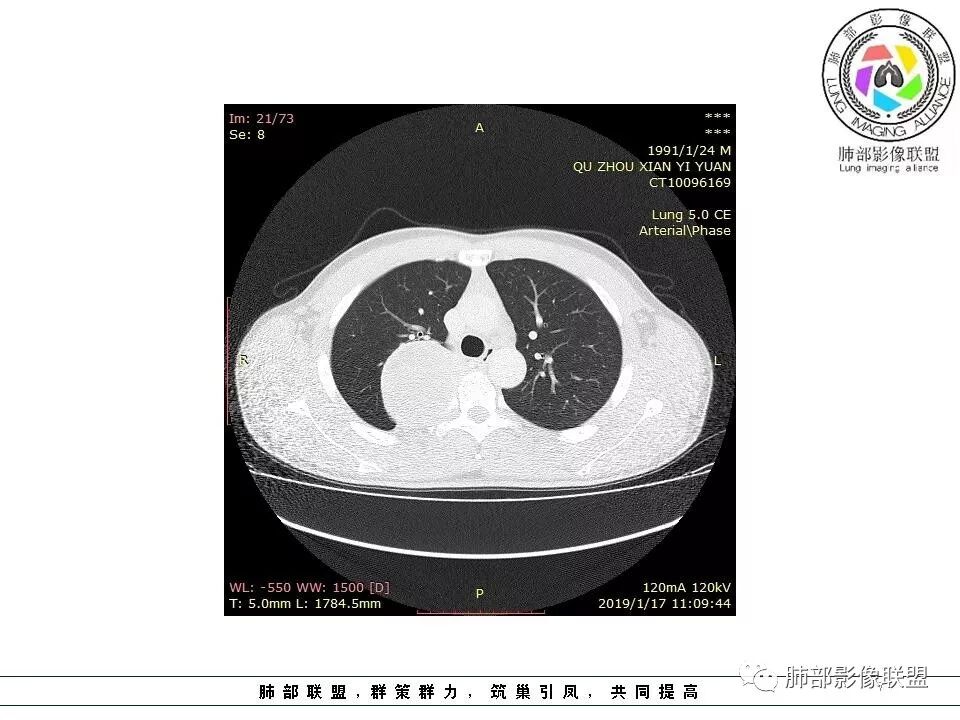

后纵隔脊柱旁占位性病变,疾病谱有神经鞘瘤,sft,节细胞瘤,髓外造血。此例有胸膜尾征,蛇纹征 ,延迟强化。考虑胸膜孤立性纤维瘤。看到有供血动脉,但不知道是哪里的血管。

后纵隔类圆形新生物,边缘光滑,胸膜尾征明显,贴近脊柱,蛇纹,血供丰富,考虑后纵隔软组织肿瘤,具体类型看不出来,鉴别神经鞘瘤。

青年男性,间断胸痛;右侧脊柱旁可见一类圆形软组织密度影,密度欠均匀,增强扫描呈轻中度持续强化,邻近肺组织及肺动脉推移,可见肋间动脉供血,部分胸膜下脂肪可见,部分层面似见与右侧椎间孔相连。考虑后纵隔神经源性肿瘤。

右侧后纵隔脊柱旁占位,边缘光滑清晰,内侧肺组织受压,外侧可见胸膜尾征,增强持续强化,并可见蛇纹血管征。考虑SFT

青年男性,右侧后纵膈肿块,有胸膜尾征,支气管被推压,定位肺外,脏胸膜?血供来自肺动脉及肋间动脉,增强后有强化,蛇纹征,考虑SFT,鉴别鞘瘤

右肺占位,跨越上叶后段、下叶背,边缘光滑,瘤肺界面清,见肺压缩缘(线样不张`强化),见胸膜尾征,胸膜下脂肪未见明显增厚,肋骨丶脊柱未见侵袭及受压,渐进性丶地图样强化,冠状位似见体循环供血

诊断:SFT(来源壁层胸膜?一般小于20%)

右后纵膈肿块,肺瘤界面清楚,胸膜尾征,邻近肺组织及支气管被推移,部分脂肪间隙存在,定位肺外来源,血供来自肋间动脉,增强后持续渐进强化,蛇纹征,考虑SFT,鞘瘤肿块内血管罕见,不考虑。

右上肺野脊柱旁软组织肿块,边缘光滑整齐,肺组织及气管右肺上叶支气管受压前移,外移,边缘可见胸膜尾征,病灶内密度不均,增强后渐进性持续强化,其内可见明显蛇纹血管征,首先考虑肺外来源,sft.可能性大

边缘光滑,宽基底与胸壁相连,跨叶裂,叶裂稍前推,血管、支气管前移。

肋间动脉供血,强化尚均匀,逐步强化